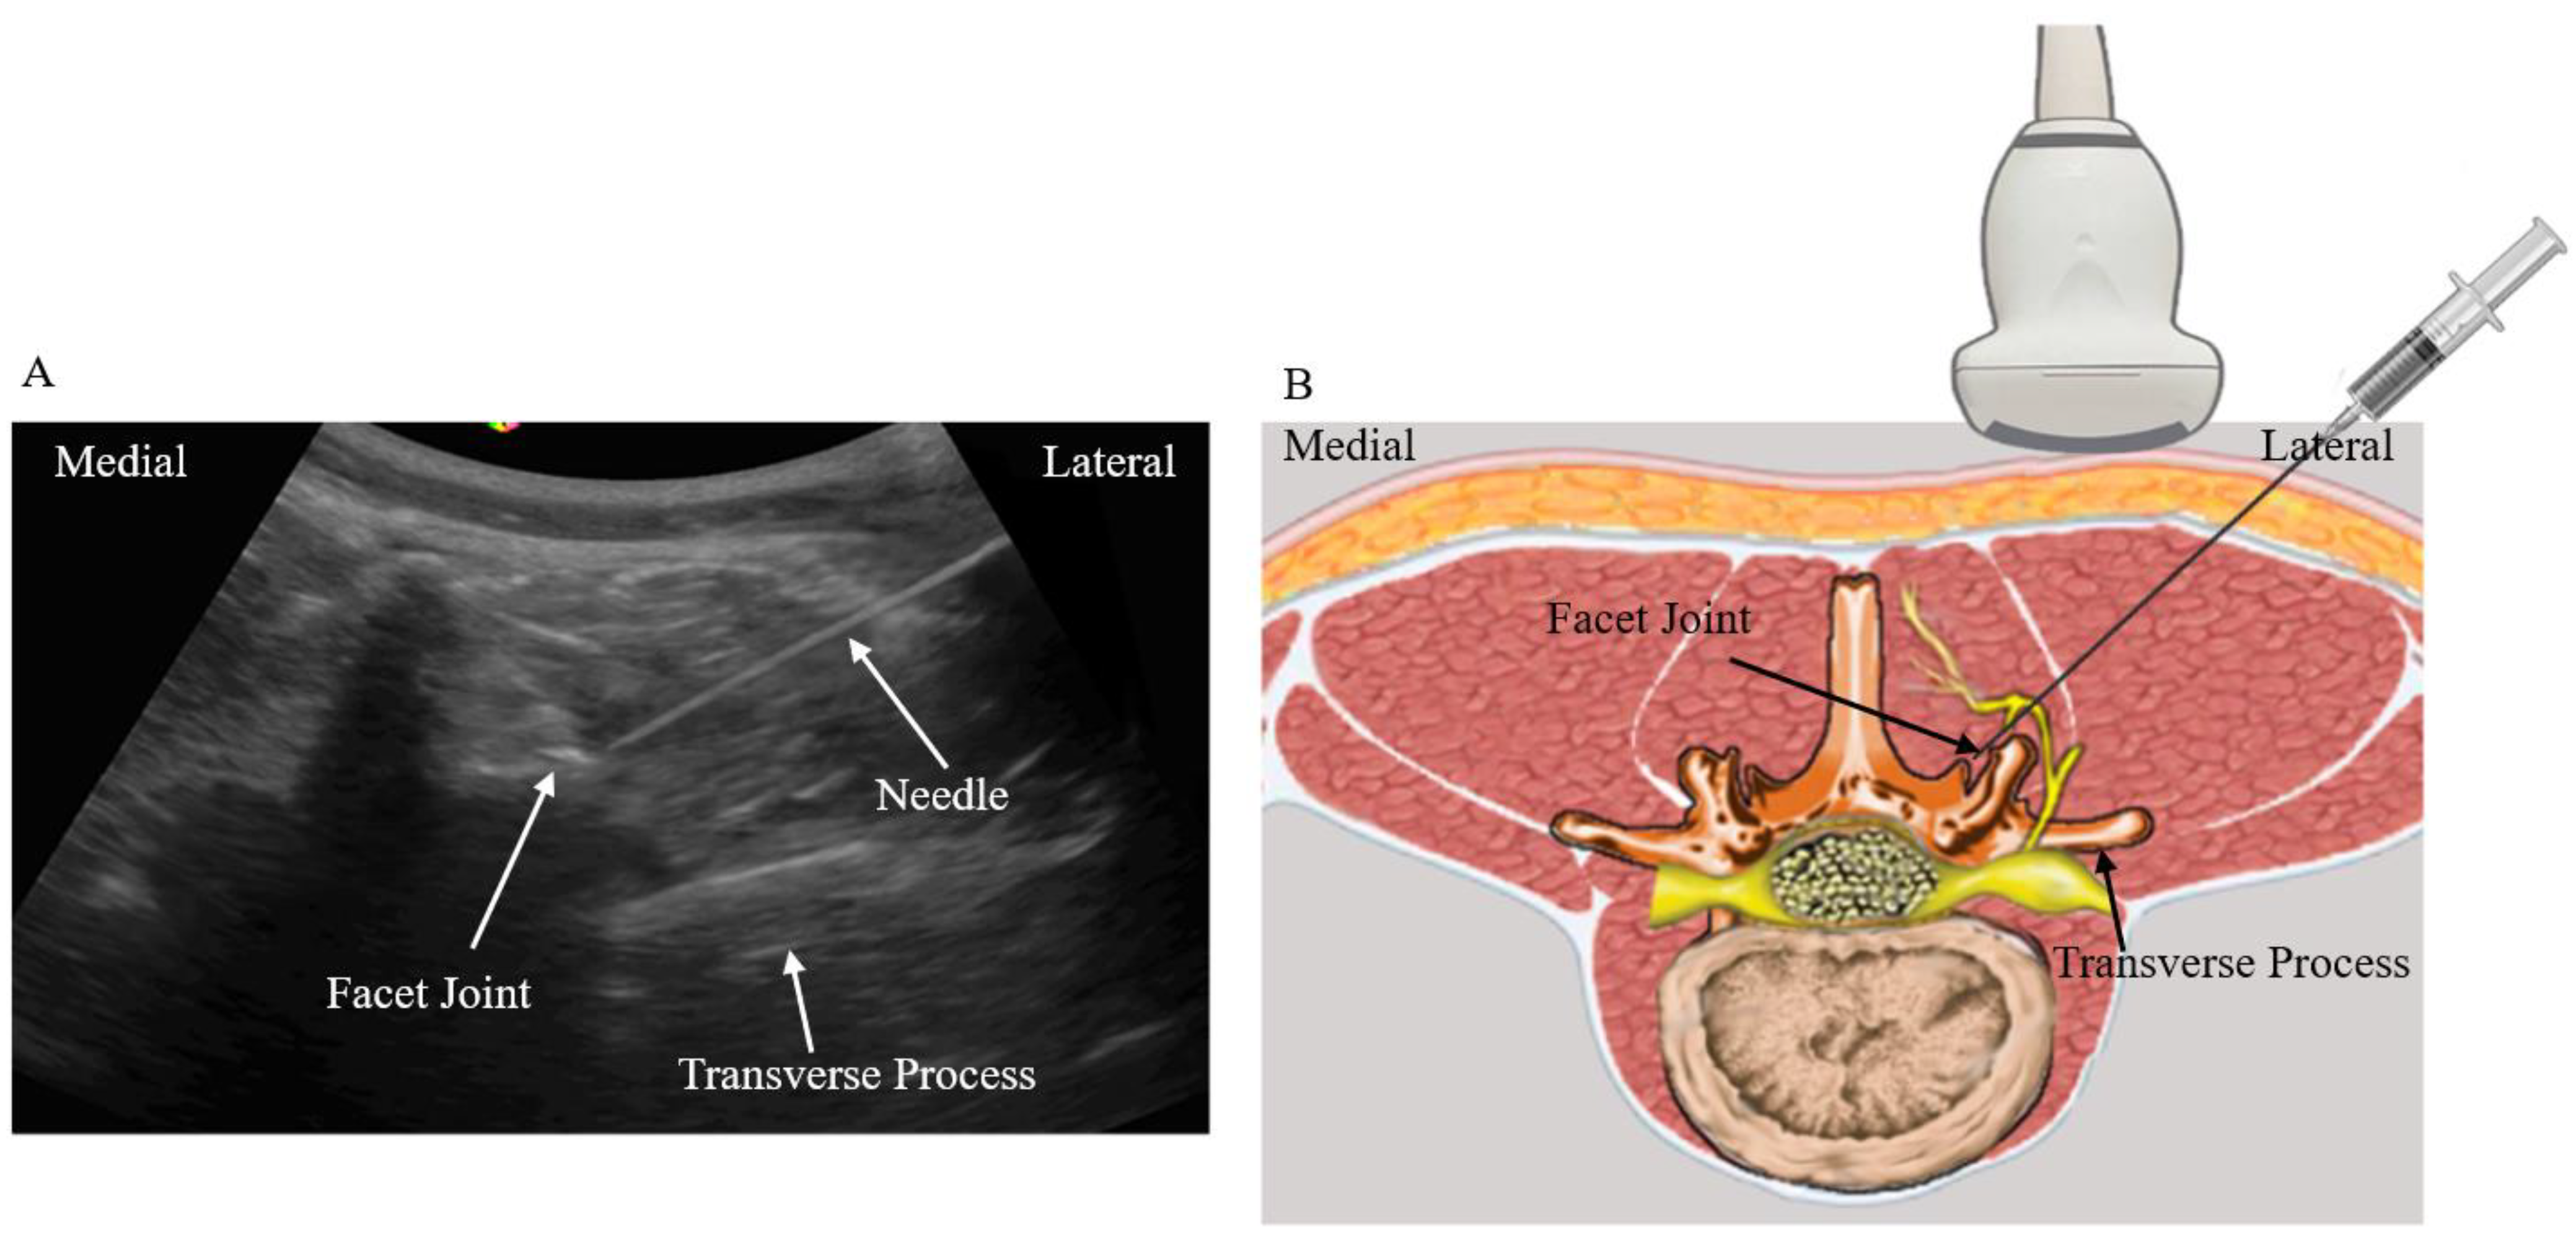

2.2. Treatment Protocols